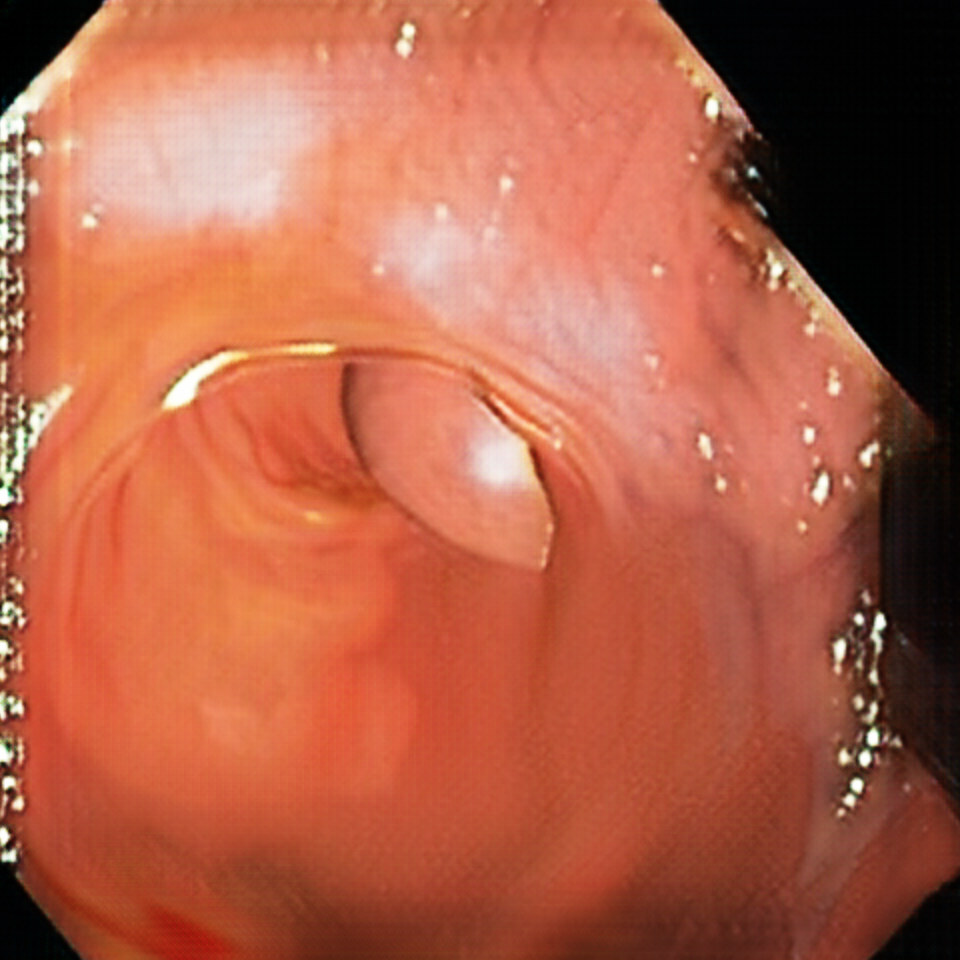

Early polyp segmentation was based in the texture and shape of the polyps. For example, Hwang et al. [8] used ellipse fitting techniques based on shape. However, some corectal polyps can be small (5mm) and are not detected by these techniques. In addition, the texture is easily confused with other tissues in the colon as can be seen in Figure 2.

Our 3D colons structure is a cone composed by 2454 faces. Vertices are randomly displaced following a normal distribution in order to simulate the tissues in the colon. Additionally, the colon structure is modified by displacing 7 segments as in Figure 3. For the textures we used a base color [0.80, 0.13, 0.18] (RGB). For each sample we shift the color to other tones of brown, orange and pink. One single polyp is used on every image, which is placed inside the colon. It can be either in the colon’s walls or in the middle. Polyps are distorted spheres with 16384 faces. Samples with polyps occupying less than 20,000 pixels are removed.

Lighting is composed by a white ambient light, two white dynamic lights that project glare into the walls, and three negative lights that project black light at the end of the colon. We found that having a dark area at the end helps CycleGAN to understand the structure of the colon. The 3D scene must be similar to real colon images because otherwise, the CycleGAN will not translate properly the images to the real-world domain. Figure 4 illustrates the images and ground truth generated by the 3D engine.

Figure 5 displays synthetic images before and after the CycleGAN domain adaptation. Note that the position of the polyps is not altered. Hence, the ground truth information generated by the 3D engine is preserved.